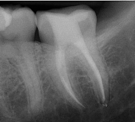

Conventional Treatment with Standard Core Restoration

Non-surgical endodontic treatment with resin core build up